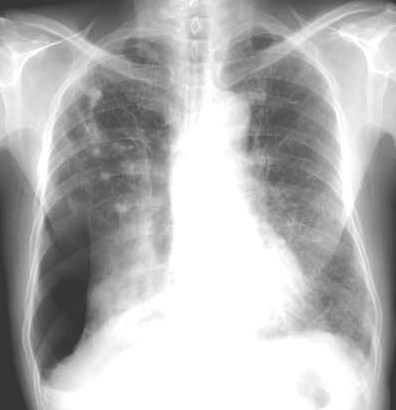

此病人咳嗽\胸闷一周,伴随发热两天.

右肺感染伴陈旧性结核;肺气肿;右侧自发性液气胸。

右侧气胸部分气体位于右上纵隔胸膜腔,右下肺萎陷且密度不均匀还应考虑肺内或者胸膜病变,建议结合侧位片,右上肺结核以纤维增殖灶和钙化灶为主,

另外,纵隔气肿.

右肺感染伴陈旧性结核;肺气肿;右侧自发性液气胸(多房性,胸膜粘连所至)